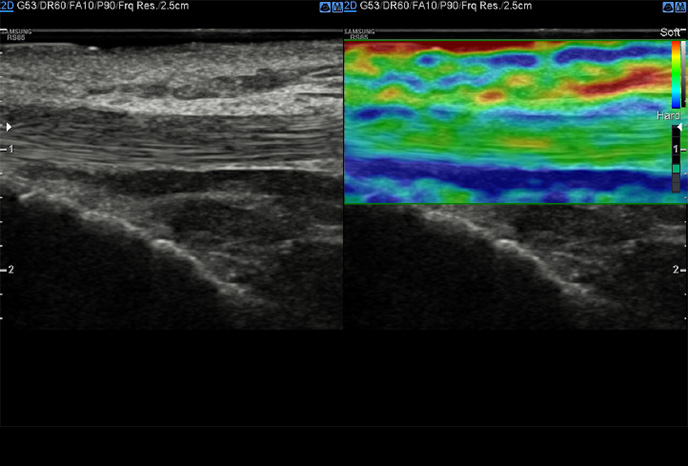

S-Shearwave Imaging ™

Neinvazivní metoda kvantifikace tuhosti tkáně

S-Shearwave Imaging ™ umožňuje neinvazivní hodnocení tuhosti tkáně / lézí v prsu a játrech, poskytnutím pokročilé úrovně diagnostických informací. Barevně mapovaný elastogram, kvantitativní měření (inkPa nebo m / s), možnost duálního zobrazení a uživatelem volitelné funkce ROI (pozice a velikost) jsou obzvláště užitečné pro přesnou diagnostiku onemocnění prsu a jater.